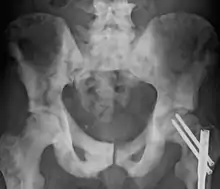

Ostéosclérose du pelvis due à un cancer.